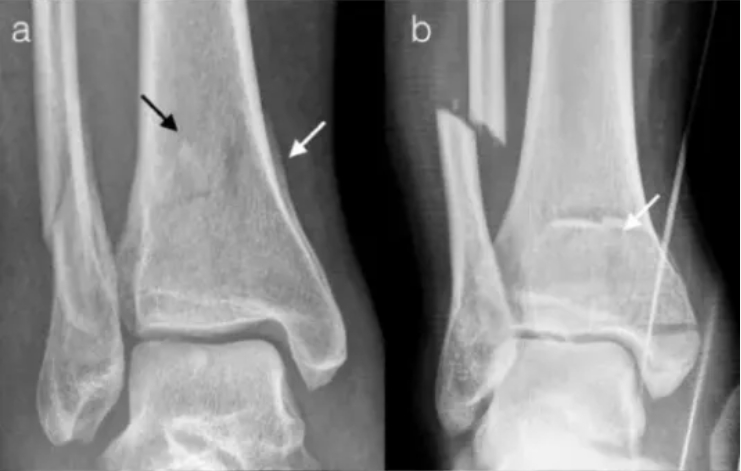

什么是Pilon骨折?

Pilon骨折是指累及胫骨远端关节面的胫骨下端骨折,常伴有腓骨骨折,多见于高处坠落、交通事故、运动损伤,严重程度取决于受伤时足部所处的位置、暴力大小、骨折粉碎程度以及软组织损伤情况。

Pilon骨折的特点是骨折累及踝关节的上负重关节面和干骺端,治疗难度大、病残率高,常导致严重的并发症如感染、畸形愈合、骨不连和创伤性关节炎。